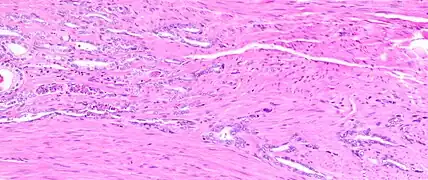

Micrograph of benign prostatic glands with corpora amylacea. H&E stain.

The prostate consists of glandular and connective tissue.[2] Tall column-shaped cells form the lining (the epithelium) of the glands.[2] These form one layer or may be pseudostratified.[4] The epithelium is highly variable and areas of low cuboidal or flat cells can also be present, with transitional epithelium in the outer regions of the longer ducts.[10] Basal cells surround the luminal epithelial cells in benign glands. The glands are formed as many follicles, which drain into canals and subsequently 12–20 main ducts, These in turn drain into the urethra as it passes through the prostate.[4] There are also a small amount of flat cells, which sit next to the basement membranes of glands, and act as stem cells.[2]

The connective tissue of the prostate is made up of fibrous tissue and smooth muscle.[2] The fibrous tissue separates the gland into lobules.[2] It also sits between the glands and is composed of randomly orientated smooth-muscle bundles that are continuous with the bladder.[11]

Over time, thickened secretions called corpora amylacea accumulate in the gland.[2]